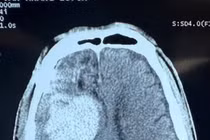

Khoa Ngoại thần kinh – Bệnh viện 19-8 vừa phẫu thuật thành công 1 trường hợp bệnh nhân nam 55 tuổi bị xuất huyết não trán – thái dương phải do ngã sau cơn động kinh.

Theo đó, bệnh nhân vào viện trong tình trạng lơ mơ, Glasgow 12 điểm, liệt nửa người trái.